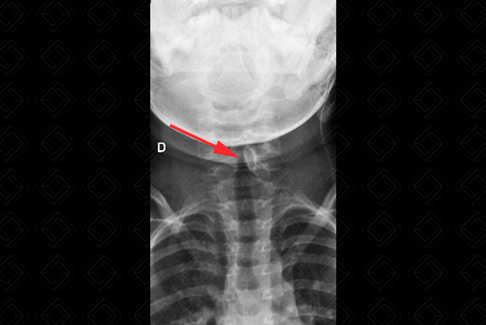

Texto alternativo para a imagem Figura 1. Créditos: Dra. Elazir Mota - Rio de Janeiro/RJ

Descrição das figuras 1 e 2: Radiografia cervical. Presença de osso omovertebral à esquerda (setas vermelhas). Diante deste achado na criança, com deformidade da cintura escapular, sempre buscar pela possibilidade de síndrome de Sprengel.

• Radiografia de coluna cervical: A avaliação inicial comumente é realizada por meio de radiografia de coluna que, na maioria dos casos, detecta com facilidade o osso omovertebral (imagens acima);